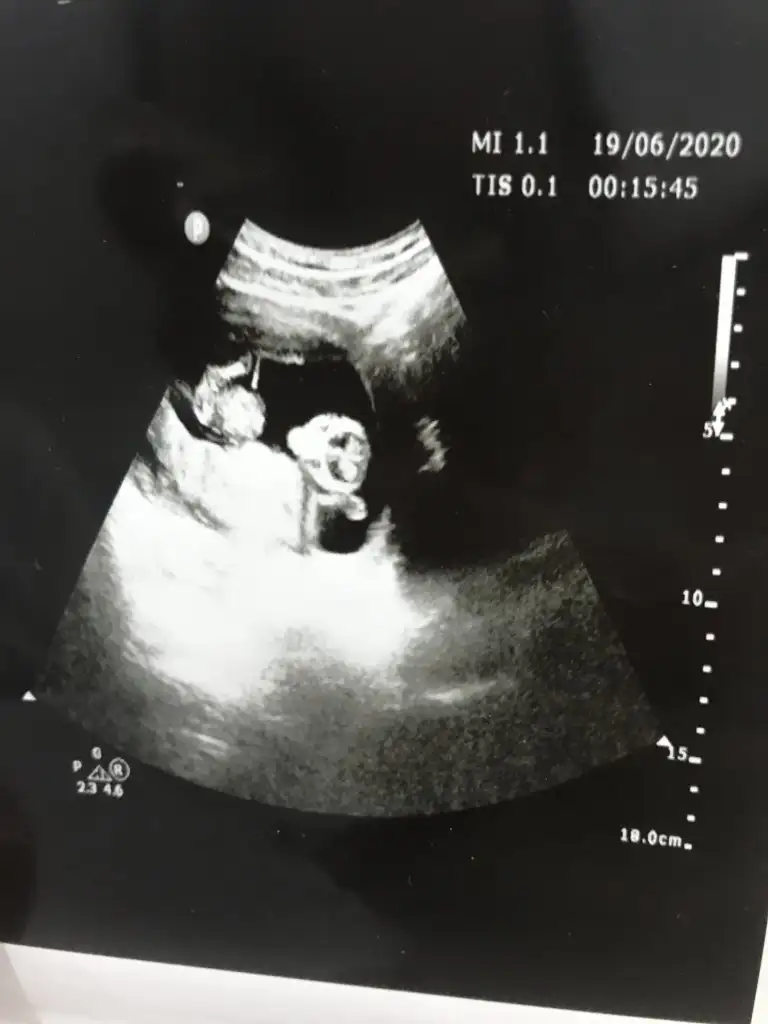

Evet erkek gibi duruyor ilk bebekmi gönlünüz erkekmi diyorŞuan resim atmaya çalışıyorum ama olmuyor

Kaç haftalık usg sanki erkek gibi eminde olmadım 11 12 13 haft usgler olmalı tekrar usg paylaşınMerhabalar tahmininizi çok merak ediyorum :)

Üçlü taramada büyük ihtimalle kız olduğu söylendiNet degil usg tek tek çekermisiniz usgler yada başka usg olursa paylaşın 12-13 haftalarda olabilir şimdilik eminde değilim kız gibi gibi emin değilim tekrar usg paylaşın